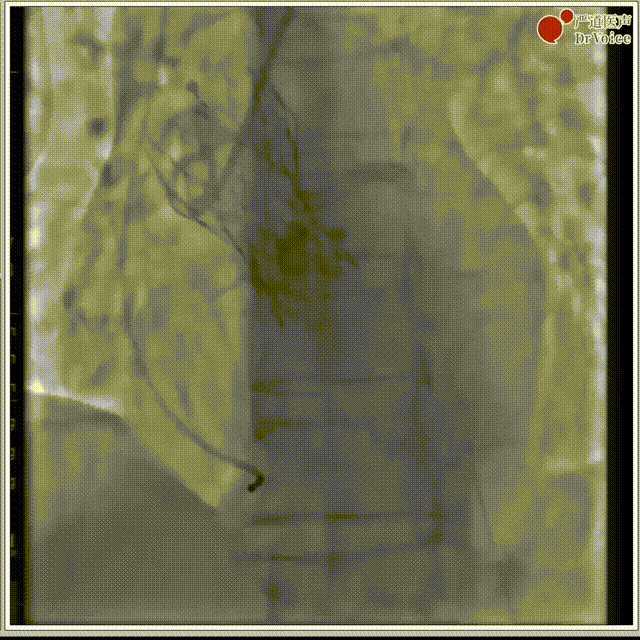

7. 复查造影,左冠有遮挡风险,遂行“烟囱支架”。

释放后左冠造影

支架释放后造影

8. 右冠显影正常,无遮挡风险,撤离导丝。

右冠造影